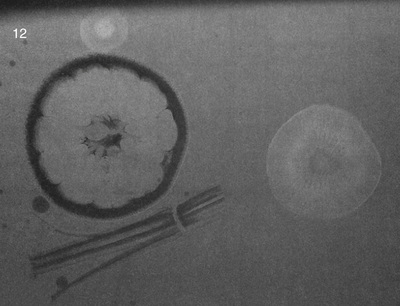

Radiographic noise also is inherent in the imaging system (Figure 10-1). A number of factors contribute to radiographic noise, including some that are under the control of radiologic technologists. Lower noise results in a better radiographic image because it improves contrast resolution.

Screen-film radiographic noise has four components: film graininess, structure mottle, quantum mottle, and scatter radiation. The principal source of radiographic noise—scatter radiation—is discussed in Chapter 11.

Film graininess refers to the distribution in size and space of silver halide grains in the emulsion. Structure mottle is similar to film graininess but refers to the phosphor of the radiographic intensifying screen. Film graininess and structure mottle are inherent in the screen-film image receptor. They are not under the control of the radiologic technologist, and they contribute very little to radiographic noise, with the exception of mammography.

Quantum mottle is somewhat under the control of the radiologic technologist and is a principal contributor to radiographic noise in many radiographic imaging procedures. Quantum mottle refers to the random nature by which x-rays interact with the image receptor.

If an image is produced with just a few x-rays, the quantum mottle will be higher than if the image is formed from a large number of x-rays. The use of very fast intensifying screens results in increased quantum mottle.